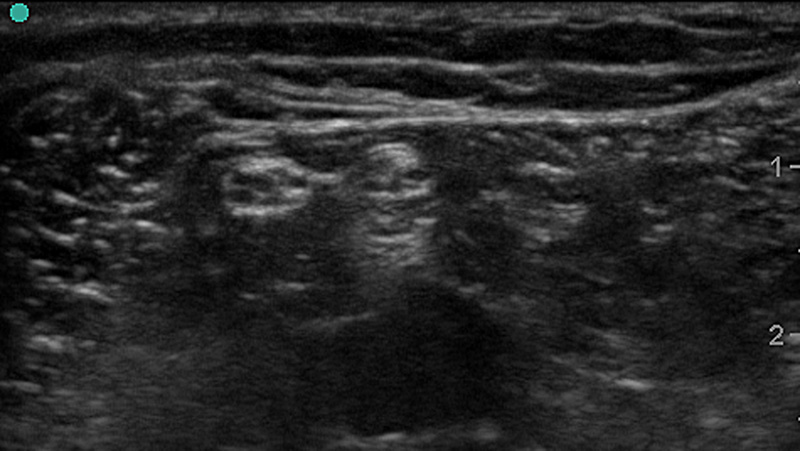

Figure 1a. Ultrasound Image of Peripheral Nerves

- Classically, nerves have a honeycomb-like appearance in cross section caused by bundling of hypoechoic nerve fascicles within hyperechoic peri- and endoneurium.

- Distal or smaller nerves contain smaller amounts of myelinated axons and can instead look like the cut end of a rope and mimic the appearance tendons.

- Nerves may be oval, round or triangular and often change shape along their course.

- The overall conformation of a peripheral nerve depends on its course and surrounding tissue.